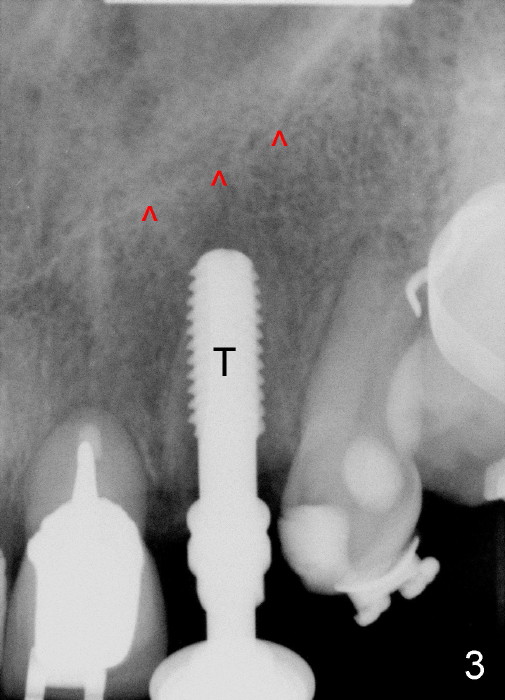

A prominent feature of implant failure in this case is pain. The patient feels that the pain is from the base of the nose. PA taken 3 days postop shows that the implant is inferior to the nasal floor (Fig.2 red ^). Clinically, the buccal gingiva continues to be erythematous 10 days postop (Fig.1). The pain is so unbearable that the implant (3.8x14 mm) is removed 10 days post placement. After repeated debridement, a 4.1 mm tap (Fig.3 T) is manually inserted with torque. A 4.1x14 mm submerged implant is placed with insertion torque < 30 Ncm, but it is placed subcrestally (Fig.4 <--). This time an immediate provisional is not provided. The flap is sutured. The pain disappears immediately. No infection is found 7 days postop (Fig.5). However, an asymptomatic vesicle is noted at the crest 3 weeks postop (Fig.6). The gingiva looks normal 2 and 3 months postop (Fig.7,8). The coronal gap dissolves 3 months postop (Fig.9 >, as compared to Fig.4), suggesting osteointegration. The implant is uncovered 4 months postop (Fig.10). Bracket is placed 5 months postop (Fig.10'). One month later, the left central incisor improves in position coronocervically (Fig.11), but the overjet needs correction by distalization of the upper anterior teeth. The implant at the site of #10 may be used as an anchorage.